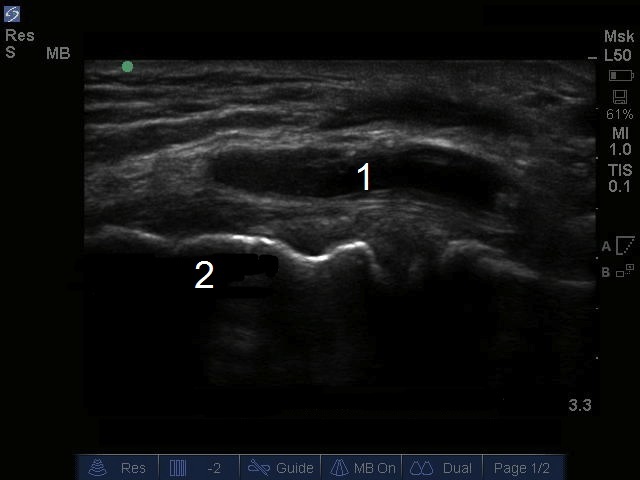

Bild: Zyste am medialen Meniskus eines Knies

Zyste am medialen Meniskus

Epicondylus medialis femoris